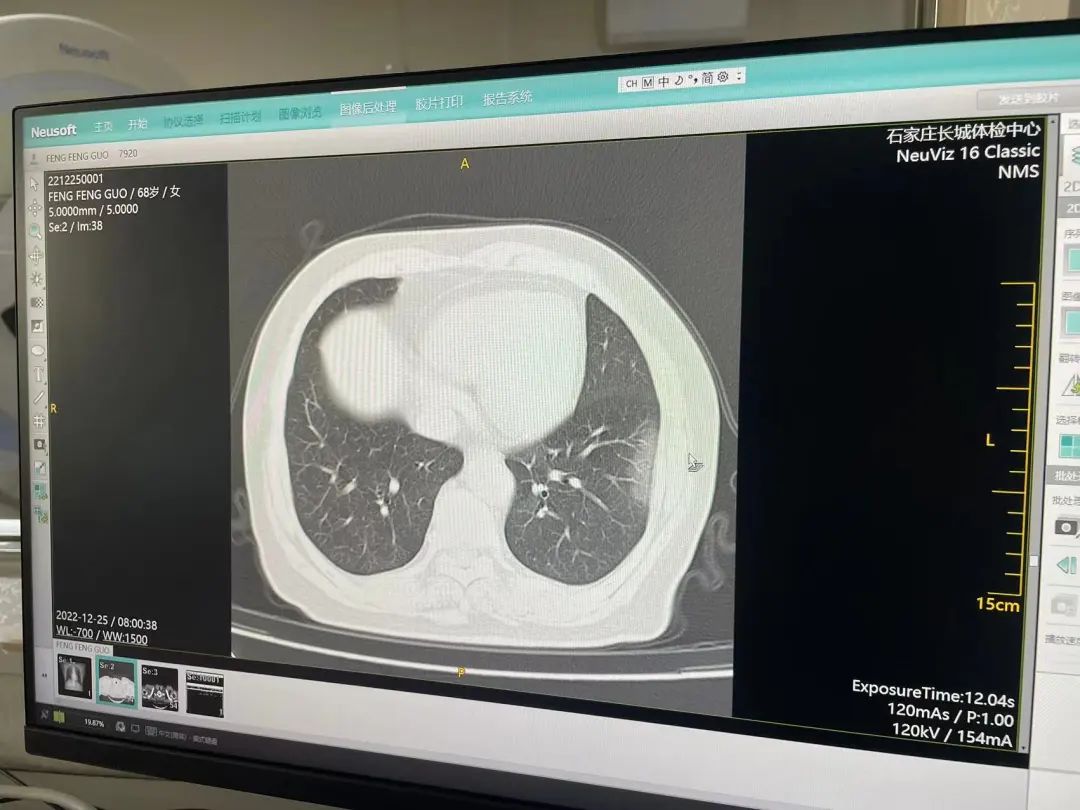

对此,建议痊愈的患者,应该给自己安排一个后续病情追踪,才不怕自己的健康被潜在危害杀个措手不及!检查肺部损伤:新冠病毒曾经影响过肺部健康以及呼吸道,所以患者康复后仍会有咳嗽、呼吸困难等状况。所以应安排一个肺部CT,新冠肺炎特征为以肺外周分布为主的肺多发磨玻璃阴影或者实变影,后期可出现肺纤维化病变,肺CT能够准确判断新冠肺炎是否对肺部造成伤害和遗留问题等。